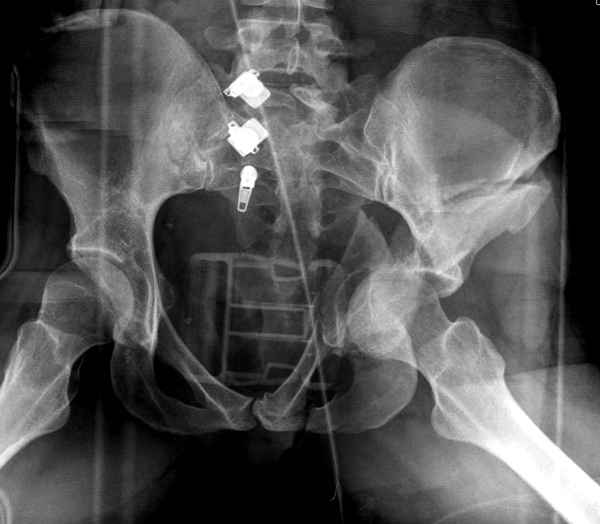

Из того минимума, что представлено, мне кажется, мы имеем дело с двухколонным переломом вертлужной впадины. Обычно медиальный (центральный) "вывих" головки встречаются в сложных двухколонных переломах со смещением.

Здесь несколько вариантов двухколонных свежих переломов, которые были оперированы из одного-заднего, а также из двух: переднего и заднего доступов.